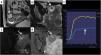

Las únicas masas ováricas con contenido sólido que se consideran Score 2 son las que son homogéneamente hipointensas en T2 e hipointensas en el estudio de difusión b1000, conocidas como lesiones «dark-dark»; estos signos son patognomónicos de los fibromas ováricos. Aunque no es necesario para su diagnóstico, los fibromas acostumbran tener una curva de bajo riesgo (fig. 4).

Fibroma ovárico con características dark-dark, O-RADS RM Score 2. La lesión ovárica izquierda es hipointensa en T2 (dark) y no restringe en difusión en el b1000 (dark), flechas en imágenes A y B. Los fibromas son las lesiones que más problemas diagnósticos ofrecen por ecografía y en la que la clasificación O-RADS RM tendrá más utilidad. C) Este fibroma presenta, además, una curva de bajo riesgo (flecha).

Dentro del grupo O-RADS Score 3 se incluyen también las masas ováricas con componente sólido que presenten una curva de captación de bajo riesgo. Estas masas acostumbran corresponder a cistoadenofibromas, que, por otra parte, muestran hipointensidad de dicha área sólida muy característica (fig. 5).

Cistoadenofibroma. A) T2 sagital. B) T2 axial. C) T1FS poscontraste. D) b1000. E) Curva de bajo riesgo. Lesión solidoquística ovárica derecha (flechas) con tejido sólido hipointenso en T2, que no restringe en difusión y que muestra una curva de captación de contraste de bajo riesgo (flechas). Corresponde a una lesión O-RADS SCORE 3 y es patognomónica de cistoadenofibroma.